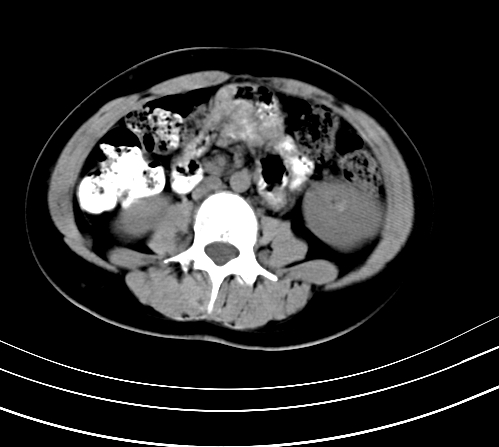

腹部平扫

动脉期

静脉期